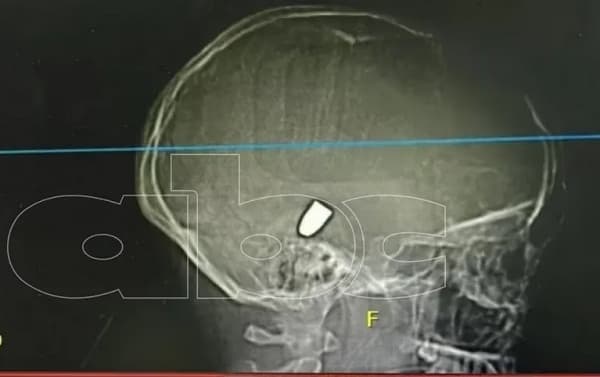

Los padres de la niña que tuvo que ser intervenida quirúrgicamente en un hospital privado de Ciudad del Este tras una grave infección con gusanos en el cuero cabelludo fueron imputados.

Los profesionales de la salud, indican que la menor estuvo en ese estado al menos 15 días y que además presenta un cuadro de desnutrición.

Con respecto al origen del cuadro grave de lesiones con miasis con el cual fue llevada la niña, el director del Hospital Los Ángeles de Ciudad del Este el doctor Guido Venialgo, dijo que es posible que se haya producido heridas en la cabeza, donde a falta de cuidado se le fueron llenando de gusanos que por la cantidad fue haciendo que se hinche la piel, de acuerdo a La Nación.